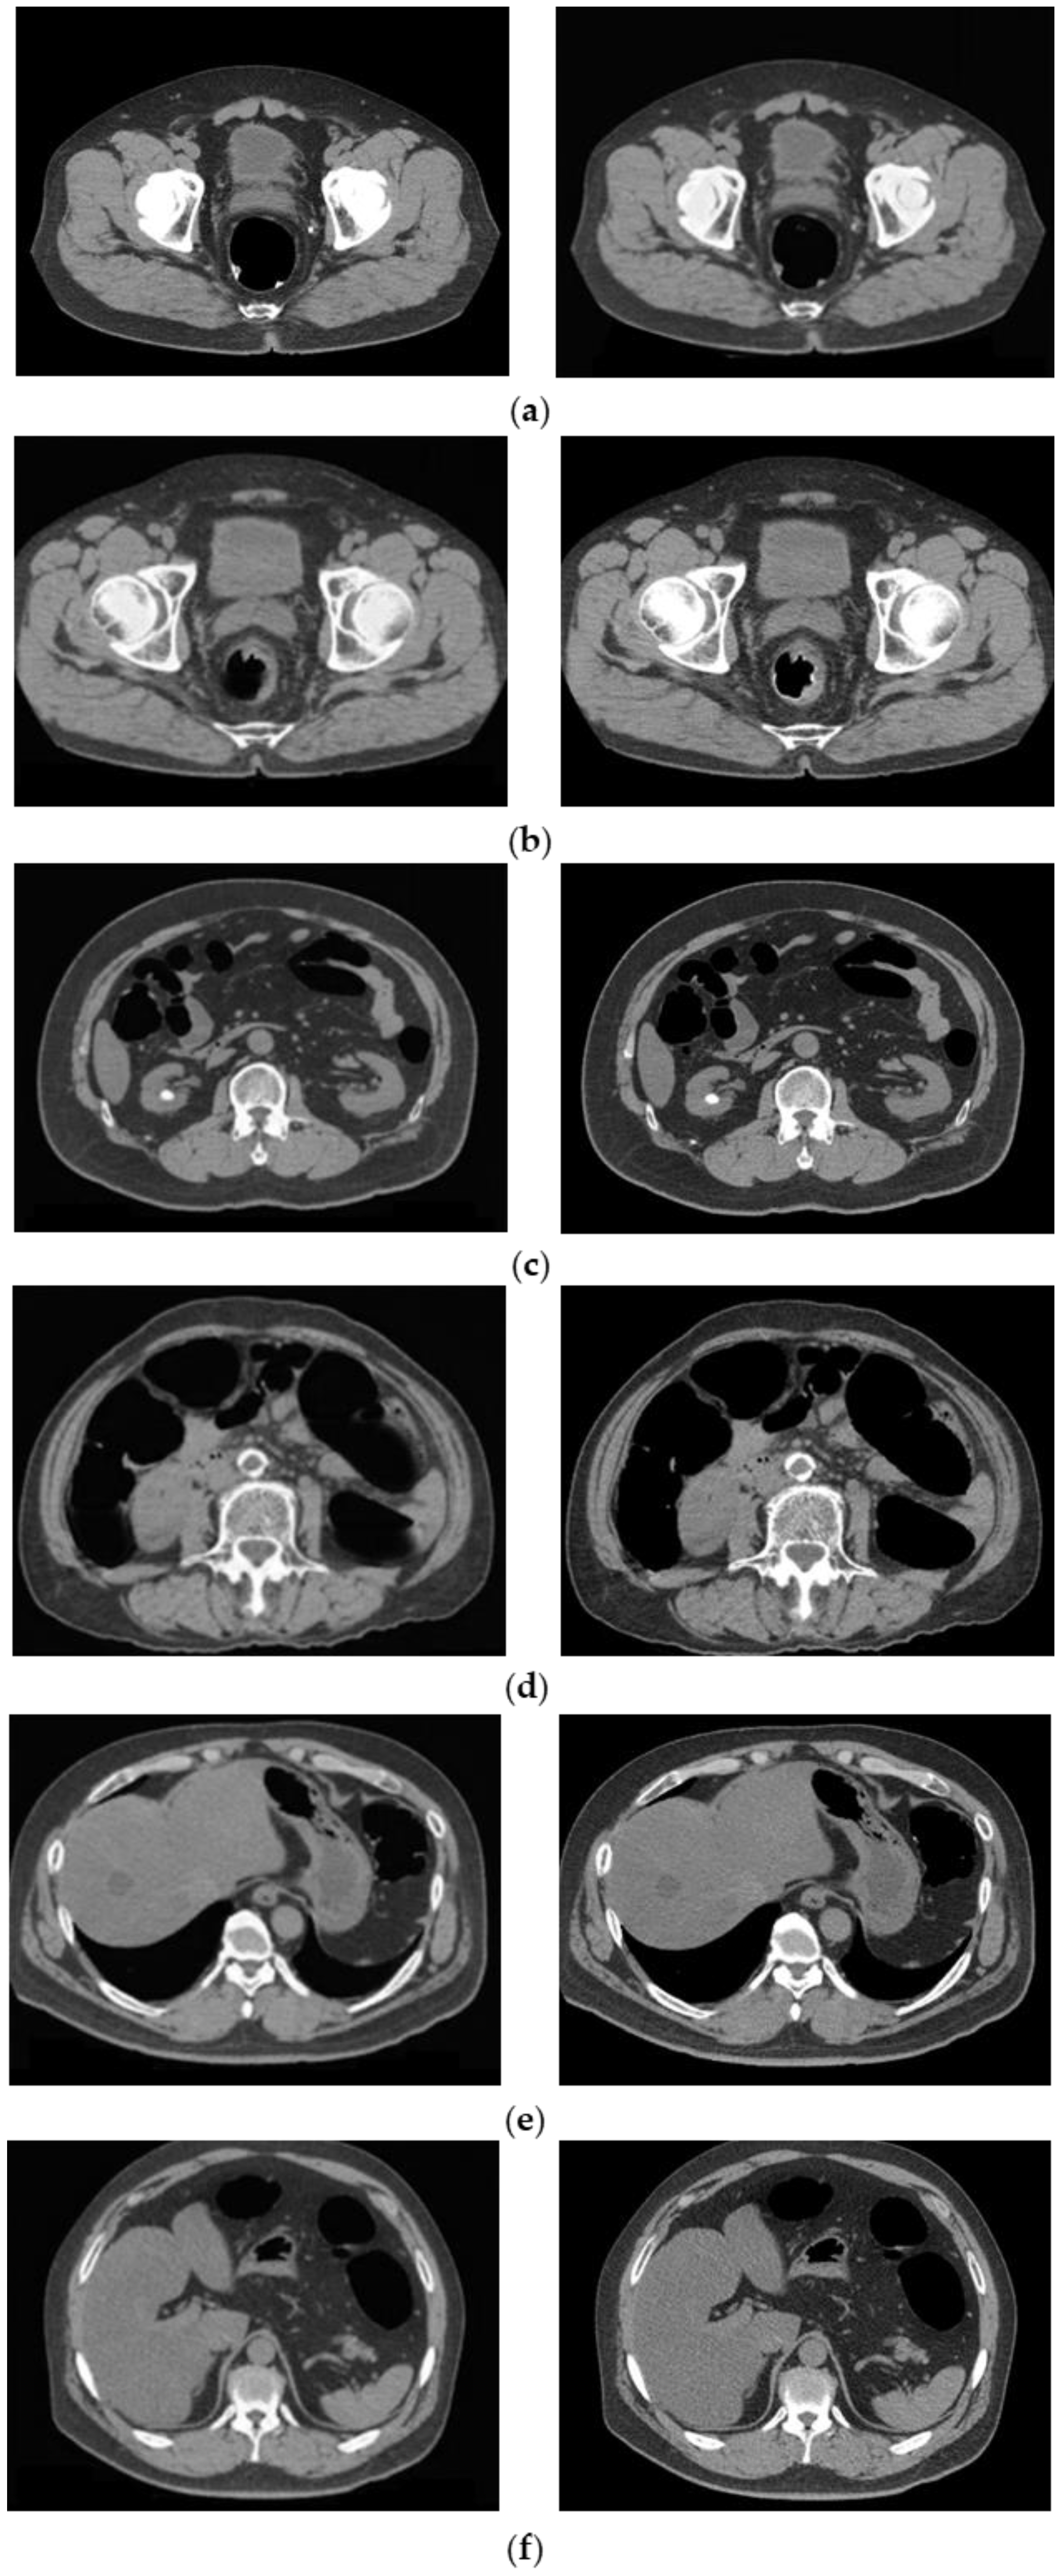

To confirm that an excess area was not removed when the barium was removed, an outline of the intestinal tract wall surface was drawn and overlapped with the original CTC image and the CycleGAN-generated image, as shown in Figure 12. In cases with good barium pretreatment (Figure 12a), poor pretreatment (Figure 12b), and lesions (Figure 12c), the intestinal wall, and lesions were not removed, and only barium was selectively removed, indicating that this technique correctly recognized and removed barium.

Figure 12.

Preservation of intestinal information by barium removal (Left: Input image and Right: output image.) (a) Good pretreatment; (b) bad pretreatment; and (c) image with lesion.